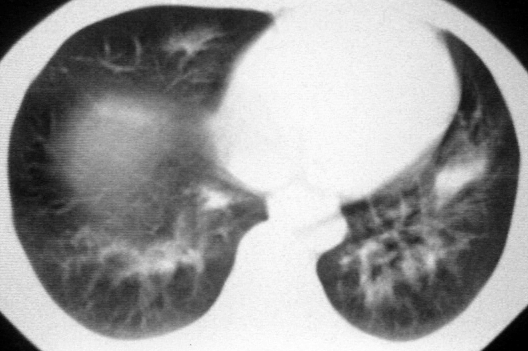

男,36岁,一月前醉酒淋雨后发热咳嗽,气短进行性加重.

抗生素治疗无效,痰检(一).

影像诊断:结核? 还有其他考虑吗?

双肺内中部见略不对称性蝶翼状高密度区,边界不清,部分呈磨玻璃样密度,并可见含气支气管征。肺门、纵隔内未见肿大淋巴结影。无胸腔积液。

考虑:1、肺炎,建议进一步查冷凝集试验除外支原体肺炎;

2、不除外霉菌感染。

双肺斑片状密度均匀病灶,边界模糊可见充气支气管征,上野多于下野,不支持结核,1肺内感染,2查肾功,中心型肺水肿待除外.

双肺中上野对称分布蝶翼样不均匀密度增高影,有支气管充气征,纵隔未见肿大淋巴结,发病突然,抗炎治疗无效,还是要考虑结核。

还是考虑肺水肿!蝶翼征.肺门增大,肺血管影增粗,!!病变累及中内带为主!要排外支原体感染.

支持: 双肺内中部见略不对称性蝶翼状高密度区,边界不清,部分呈磨玻璃样密度,并可见含气支气管征。肺门、纵隔内未见肿大淋巴结影。无胸腔积液。